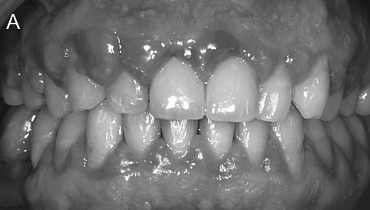

또한 사진의 경우도 주의깊게 봐야 합니다.

조명이나 각도를 달리해서 마치 극적인 변화가

있었던 것처럼 보이게 하는 경우가 많거든요.

동일한 조건에서 촬영된 전후 사진인지,

시술 직후가 아닌 충분한 회복 기간을 둔 후의

사진인지 확인하는 것이 중요합니다.

| 본 게시물은 의료광고법 제56조 1항을 준수하여, 의료 정보 제공 및 병원 홍보를 목적으로 디데이치과의원에서 직접 작성하였습니다.다만, 블로그에서 제공해 드리는 정보는 참조용으로만 활용하시고, 정확한 개인의 증상 파악은 의료기관에 직접 내방하시어 의료진을 통해 확인하실 것을 권유 드립니다.치과에서 진행되는 모든 시술 및 수술(임플란트 포함)은 개인에 따라 부작용 (염증, 출혈, 부기, 신경 손상 등) 가능성이 있습니다. 따라서 사전에 의료진과 충분한 상담을 통해 결정하시길 바랍니다.게시물의 치료 사진은 실제 본원에서 모든 치료 과정을 마친 환자분의 동의하에 촬영되었습니다. 전후 사진은 동일인이며, 동일 조건하에 촬영되었음을 밝힙니다. |